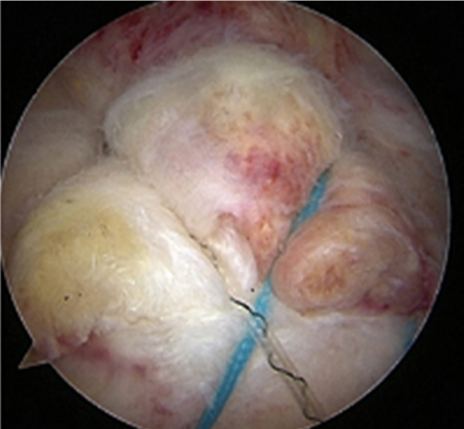

관절내시경을 통해 손상되고 찢어진 회전근개를 다듬어 주고 필요하다면 봉합까지 해주는 수술이 시행됩니다.

관절내시경 수술 전

찢어지고 파열된 회전근개 모습

관절내시경 수술 후

회전근개를 다듬고 봉합해준 모습

ㆍ환자 동의를 받은 자료이며, 이미지 사진은 실물과 다를 수 있습니다.

ㆍ2016.09.27 관절내시경 당일 치료 전, 후 사진입니다.